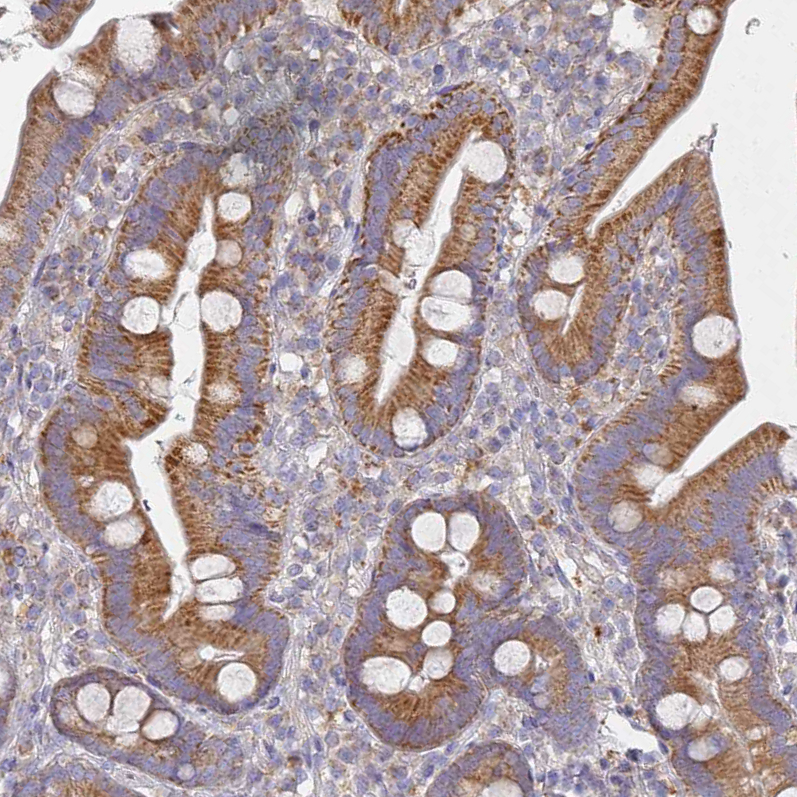

Immunohistochemical staining of human duodenum shows moderate cytoplasmic positivity in glandular cells.